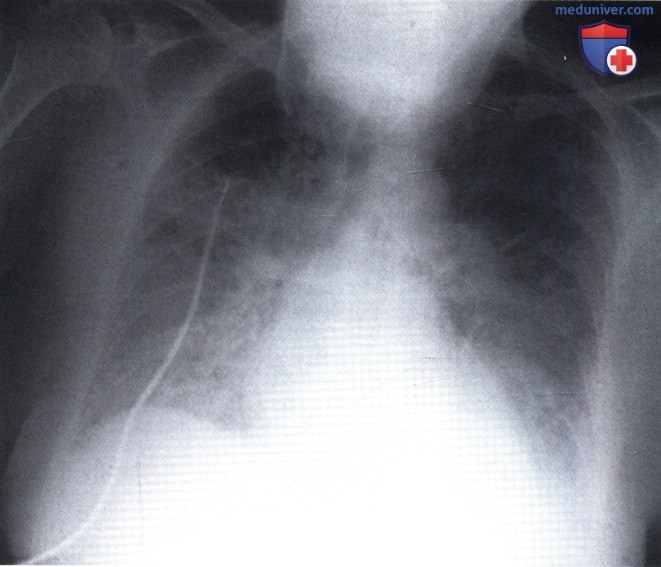

Фотографии, демонстрирующие обнаруженное усиление легочного рисунка

Раздел: Фотодневник открытий